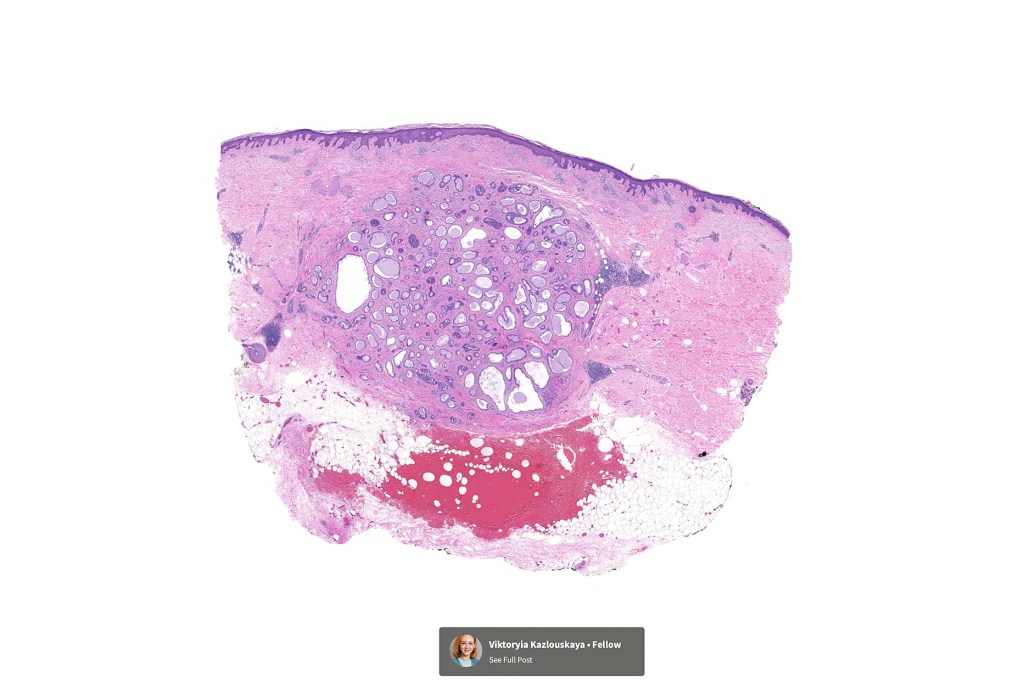

Histological features

•Circumscribed nodule composed of ducts & cysts embedded in a dense fibrous stroma sometimes associated with lymphoid aggregates/germinal centers

•Ducts lined by double-layered epithelium- small inner, uniform cells with eosinophilic cytoplasm & vesicular/hyperchromatic nuclei with small nucleoli & outer myoepithelial cells

•No pleomorphism and mitoses are sparse of absent

•Pseudo-papillae (devoid of a fibrovascular core) are often conspicuous

Absense of true papillae (i.e with a fibrovascular core)

•Variable cribriform pattern